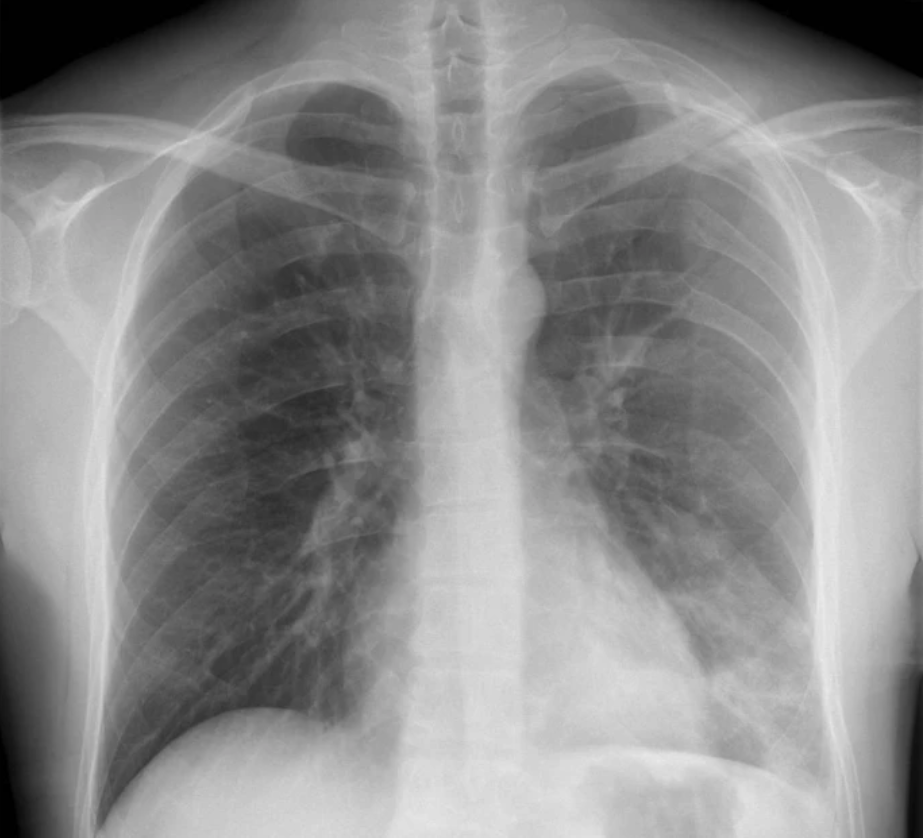

左侧锁骨骨干骨折伴多发性肋骨骨折作为伴随损伤